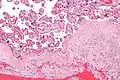

Acute choriodeciduitis, with neutrophils seen in the chorion and decidua.

The decidua has a histologically-distinct appearance, displaying large polygonal decidual cells in the stroma. These are enlarged endometrial stromal cells, which resemble epithelium (and are referred to as "epithelioid").